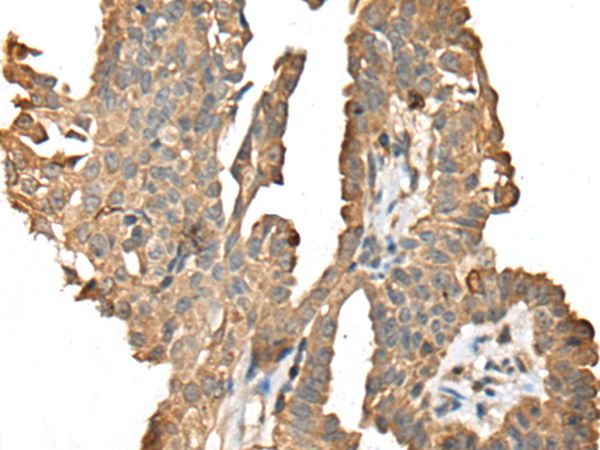

IHC positive control: |

Human gastric cancer and human thyroid cancer |